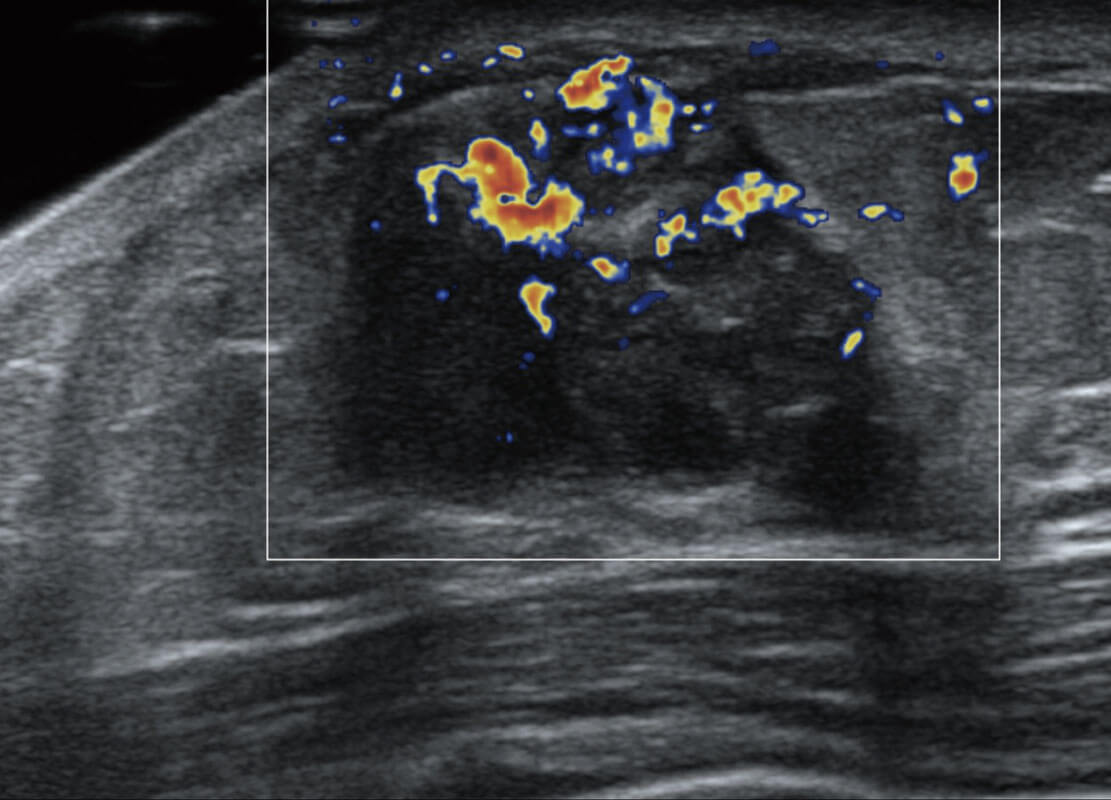

乳腺超声 / 新生儿

P60搭载宽频带线阵探头、宽景成像、弹性成像技术,为您提供乳腺应用方案。P60支持高频相控阵探头、线阵探头、腹部高频探头、腹部微凸探头等,丰富的探头群搭载敏感的彩色血流成像,适用于新生儿多种脏器检测要求,满足新生儿筛查需求。

• 乳腺导管癌

• 乳腺癌显微血流